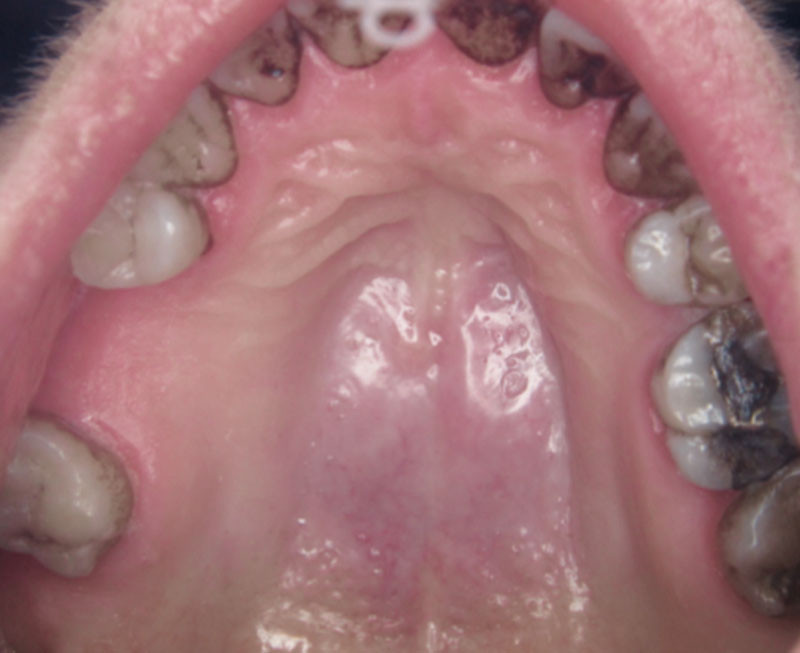

Femme de 46 ans qui a consulté pour une douleur palatine médiane présente depuis quatre mois.

Depuis quatre mois, la patiente se plaint d’une douleur palatine localisée, continue.